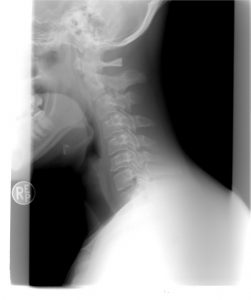

Bóle szyi i karku mogą dotykać wiele osób. Poznaj banalne i skuteczne ćwiczenie Rolanda Brachta, które błyskawicznie uwalnia napięcie! Nie musisz niepotrzebnie się męczyć z bólem, ponieważ możesz sobie pomóc w prosty i szybki sposób.

Usiądź wygodnie, najlepiej na krześle. Wyprostuj się. Na czubku głowy połóż obie ręce. Wzrok miej skierowany prosto przed siebie. Z rękami na głowie delikatnie pociągnij szyję, by zgiąć ją do przodu.

Jeśli czujesz pieczenie w karku, zachowaj spokój, to normalne. Małymi kroczkami powinieneś odczuwać rozciąganie się szyi w dół. Pamiętaj, by rękami nie ciągnąć głowy w przód. Jedynie, gdy wydychasz powietrze, możesz, bez nacisku, przemieścić głowę nieco niżej.

Uwaga! Pamiętaj, aby być zawsze wyprostowanym. Ciągnij wyłącznie z pomocą dłoni na głowie. Warto mieć obok siebie kogoś, kto skontroluje to, w jakiej pozycji są Twoje plecy. Głowa znajdująca się nisko powinna mieć na sobie wyłącznie lewą rękę. Prawa powinna znajdować się na ramieniu i być zgięta w łokciu. W takiej pozycji pociągnij delikatnie do tyłu. Nie przechylaj głowy na bok. Weź głęboki oddech. Potem dokonaj zamiany stron.